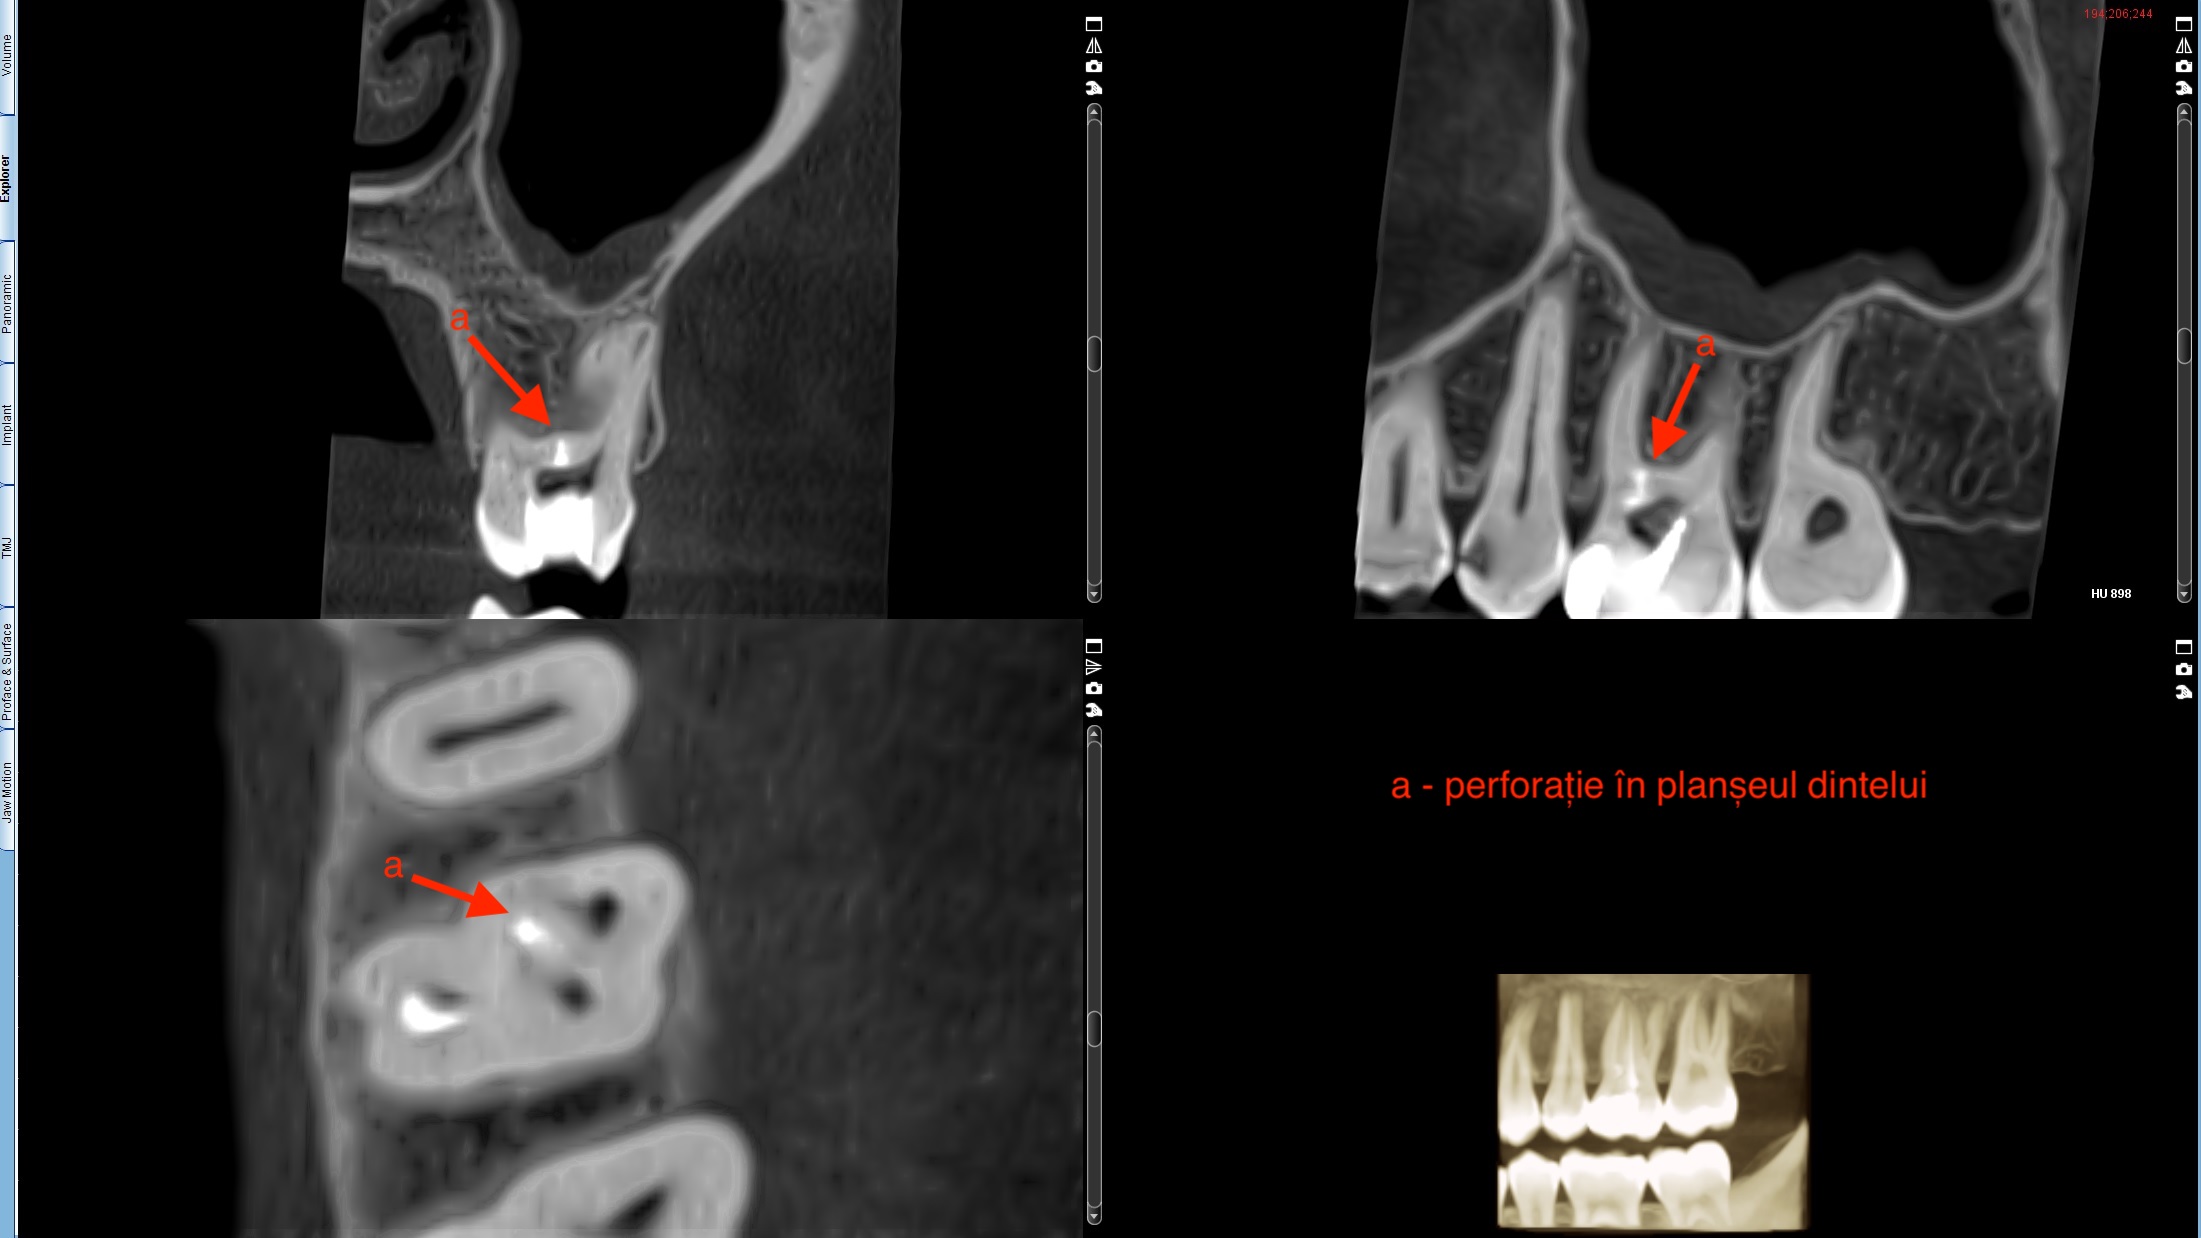

După ce s-a evaluat cu atenție cazul în clinica noastră, i s-a explicat pacientului că va fi nevoie de o radiografie tridimensională pentru a aprecia cu exactitate morfologia dintelui. La analiza radiografiei 3D am putut observa nivelul la care se afla perforația care urma să fie închisă (Figura 1) dar și nivelul la care s-a fracturat instrumentul rotativ (Figura 2).

Figura 2. Radiografia 3D prezentând nivelul la care s-a fracturat instrumentul